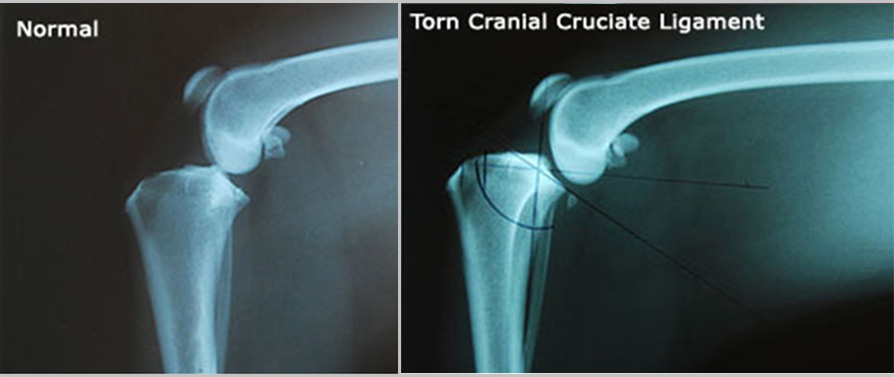

Radiographs (X-rays) Of A Dog's Knee With A Torn Cranial Cruciate Ligament

Following initial diagnosis and as part of the evaluation for TPLO surgery, the knees will be radiographed. In the x-rays below, the first X-ray shows a normal leg with the femur in proper position on top of the tibia. In the second x-ray, the ligament is torn, and the femur has slid backwards down the slope of the tibia. On the abnormal x-ray, the doctor has taken some measurements and marked the x-ray in preparation for the TPLO procedure.